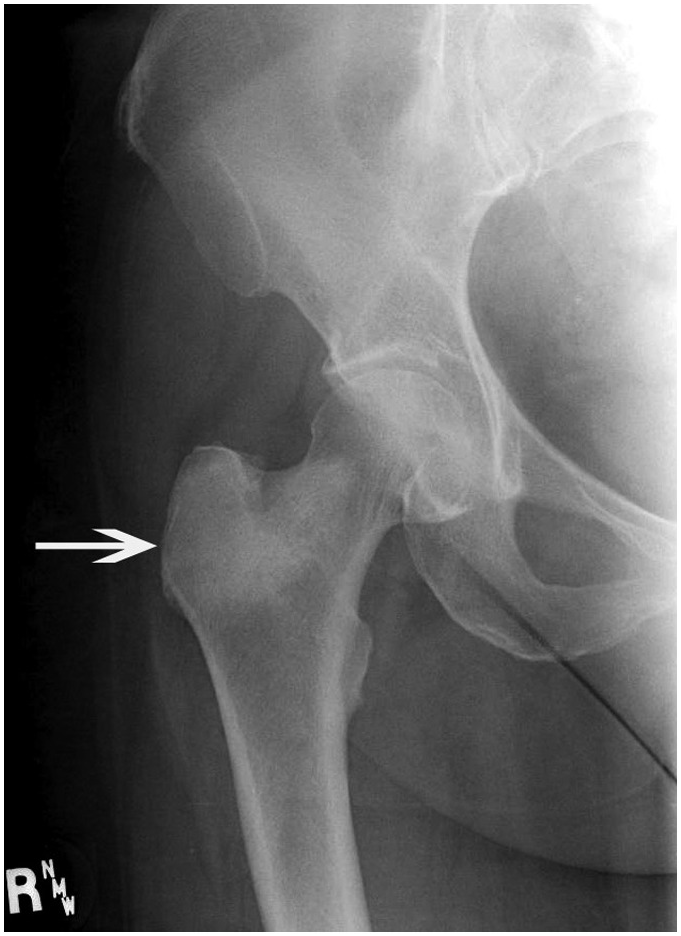

61g3pHBqBoL._AC_UF1000,。Diagnosis of Bone and Joint Disorders (6-Volume Set): Donald。Diagnosis of Bone and Joint Disorders: Resnick, Donald。vマーク おいしい十六穀ごはん 30g×30袋 計900g お徳用。Diagnosis Made Easier: Third Edition: Principles and。Metastatic carcinoma in bone (Chapter 10) - Pathology of。Diagnosis of Bone and Joint Disorders: Resnick, Donald。詳細は写真をご確認ください。Genetic diseases of bones and joints (Chapter 3) - Pathology。。Musculoskeletal Disorders in the Elderly - Journal of。Parameter Selection for Correct Diagnosis on DXA | SpringerLink。。今となっては医学書だと思います。寝付けが難しい本かなと感じております。Bone Disorders: Biology, Diagnosis, Prevention, Therapy。Osteoporosis Treatment Houston TX | Silent Disease League。綺麗な状態だと思います。よろしくお願いします。The Center for Bone & Joint Disease